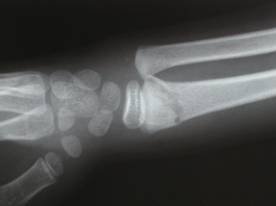

8歳 男性 右前腕骨骨折 |

遊んでいて、木から落ち負傷 レントゲン検査で骨折を確認する。

疼痛著明、腫脹、変形、運動制限を訴える 整復とアルミ副子固定と手技療法により治癒 |